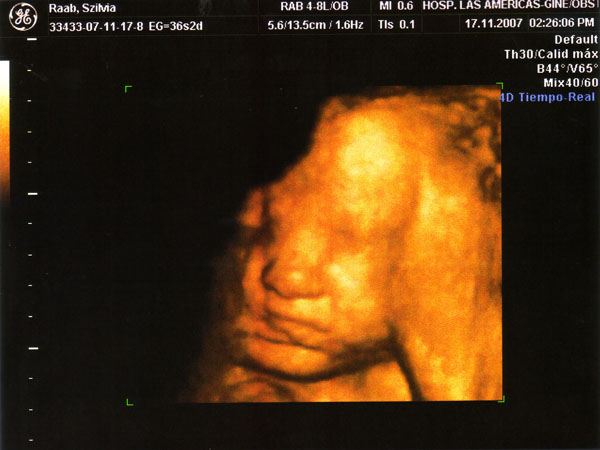

Nagyon aranyos a kép Marcusról!!!